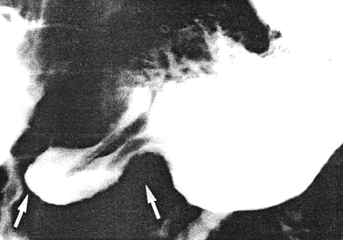

Case 37.4. M.J., 63 year old female was admitted for ischaemic heart disease, loss of weight and anorexia. She was a known case of non-insulin dependent diabetes mellitus and had received oral therapy for the previous 10 years. There was severe target organ involvement with diabetic retinopathy. Upper gastro-intestinal radiological examination showed a constant contraction of the pyloric sphincteric cylinder which remained unchanged throughout the examination (Fig. 37.4); this was thought to be compatible with early diabetic gastroparesis.

![]() |

| Fig. 37.4. Case M.J. Permanent contraction of pyloric sphincteric cylinder (arrows) |